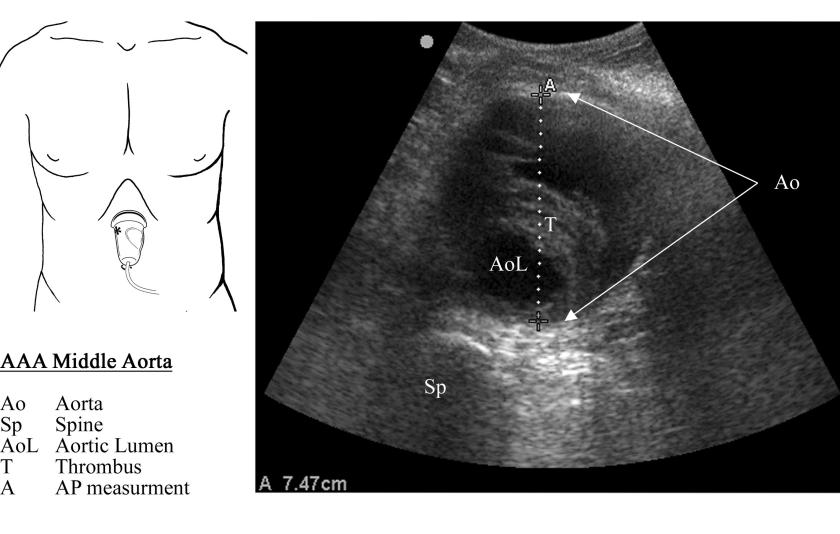

Pocket Reference Sample 1